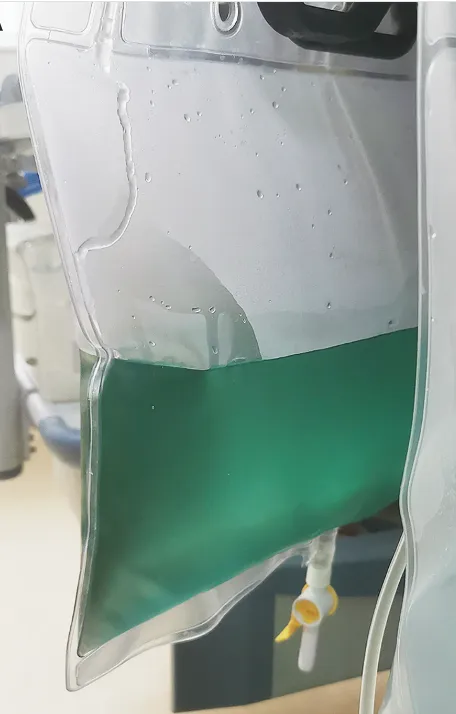

Hematúria pós infecção, caso clínicos para auxiliar no entendimento de causas glomerulares comuns e raras...